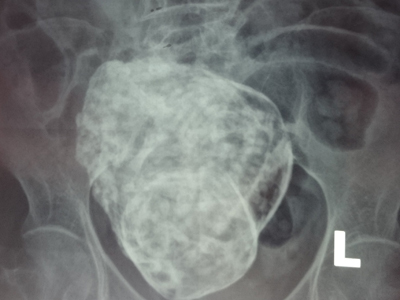

| Hình ảnh "bào thai đá" trong bụng bà cụ 76 tuổi. |

Trưa 24-3, bác sĩ Lê Quang Vinh, PGĐ - Bệnh viện Đa khoa khu vực Cam Ranh cho biết, vừa đưa cụ bà 76 tuổi, được chẩn đoán có thai chết lưu trong ổ bụng “thai đá” ra Bệnh viện Đa khoa tỉnh Khánh Hòa để chụp MRI, nhằm xác định khối thai có ảnh hưởng gì đến các bộ phận cơ thể xung quanh, qua đó có hướng giải quyết phù hợp và tốt nhất cho sức khỏe của cụ bà. Tuy nhiên, kết quả phải đợi đến chiều tối nay, hoặc sáng mai (25-3) sẽ có kết quả cụ thể.

Trước đó, lãnh đạo Bệnh viện Đa khoa thành phố Cam Ranh (tỉnh Khánh Hòa) cho biết, bệnh viện đã phát hiện cụ bà 76 tuổi (trú tại phường Cam Lộc, TP Cam Ranh) mang trong bụng một bào thai đã chết lưu từ rất lâu. Cũng theo vị bác sĩ này, đây là trường hợp hiếm gặp, rất hy hữu trong y khoa của thế giới.

Theo thông tin ban đầu, khi đi khám, cụ bà nói rằng, gần đây bà cảm thấy đau vùng thắt lưng nên mới đến Bệnh viện Đa khoa Cam Ranh để khám bệnh. Kết quả chụp phim X-quang cho thấy, có hình hài bào thai nằm trong ổ bụng của bà. Các bác sĩ dự đoán, bào thai này rất có thể đã hình thành cách đây gần 30 năm trước.